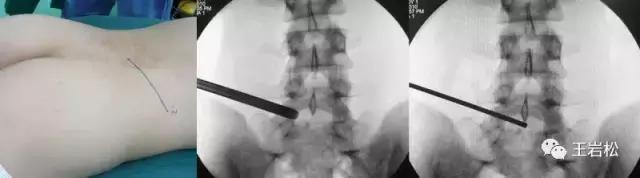

任何手术都有风险,椎间孔镜手术也一样,只是椎间孔镜手术风险较低。在穿刺和建立通道时会实时术中X线透视确保进度安全,手术时术野全程暴露于显示器下,术者十分清晰地掌握手术全局。